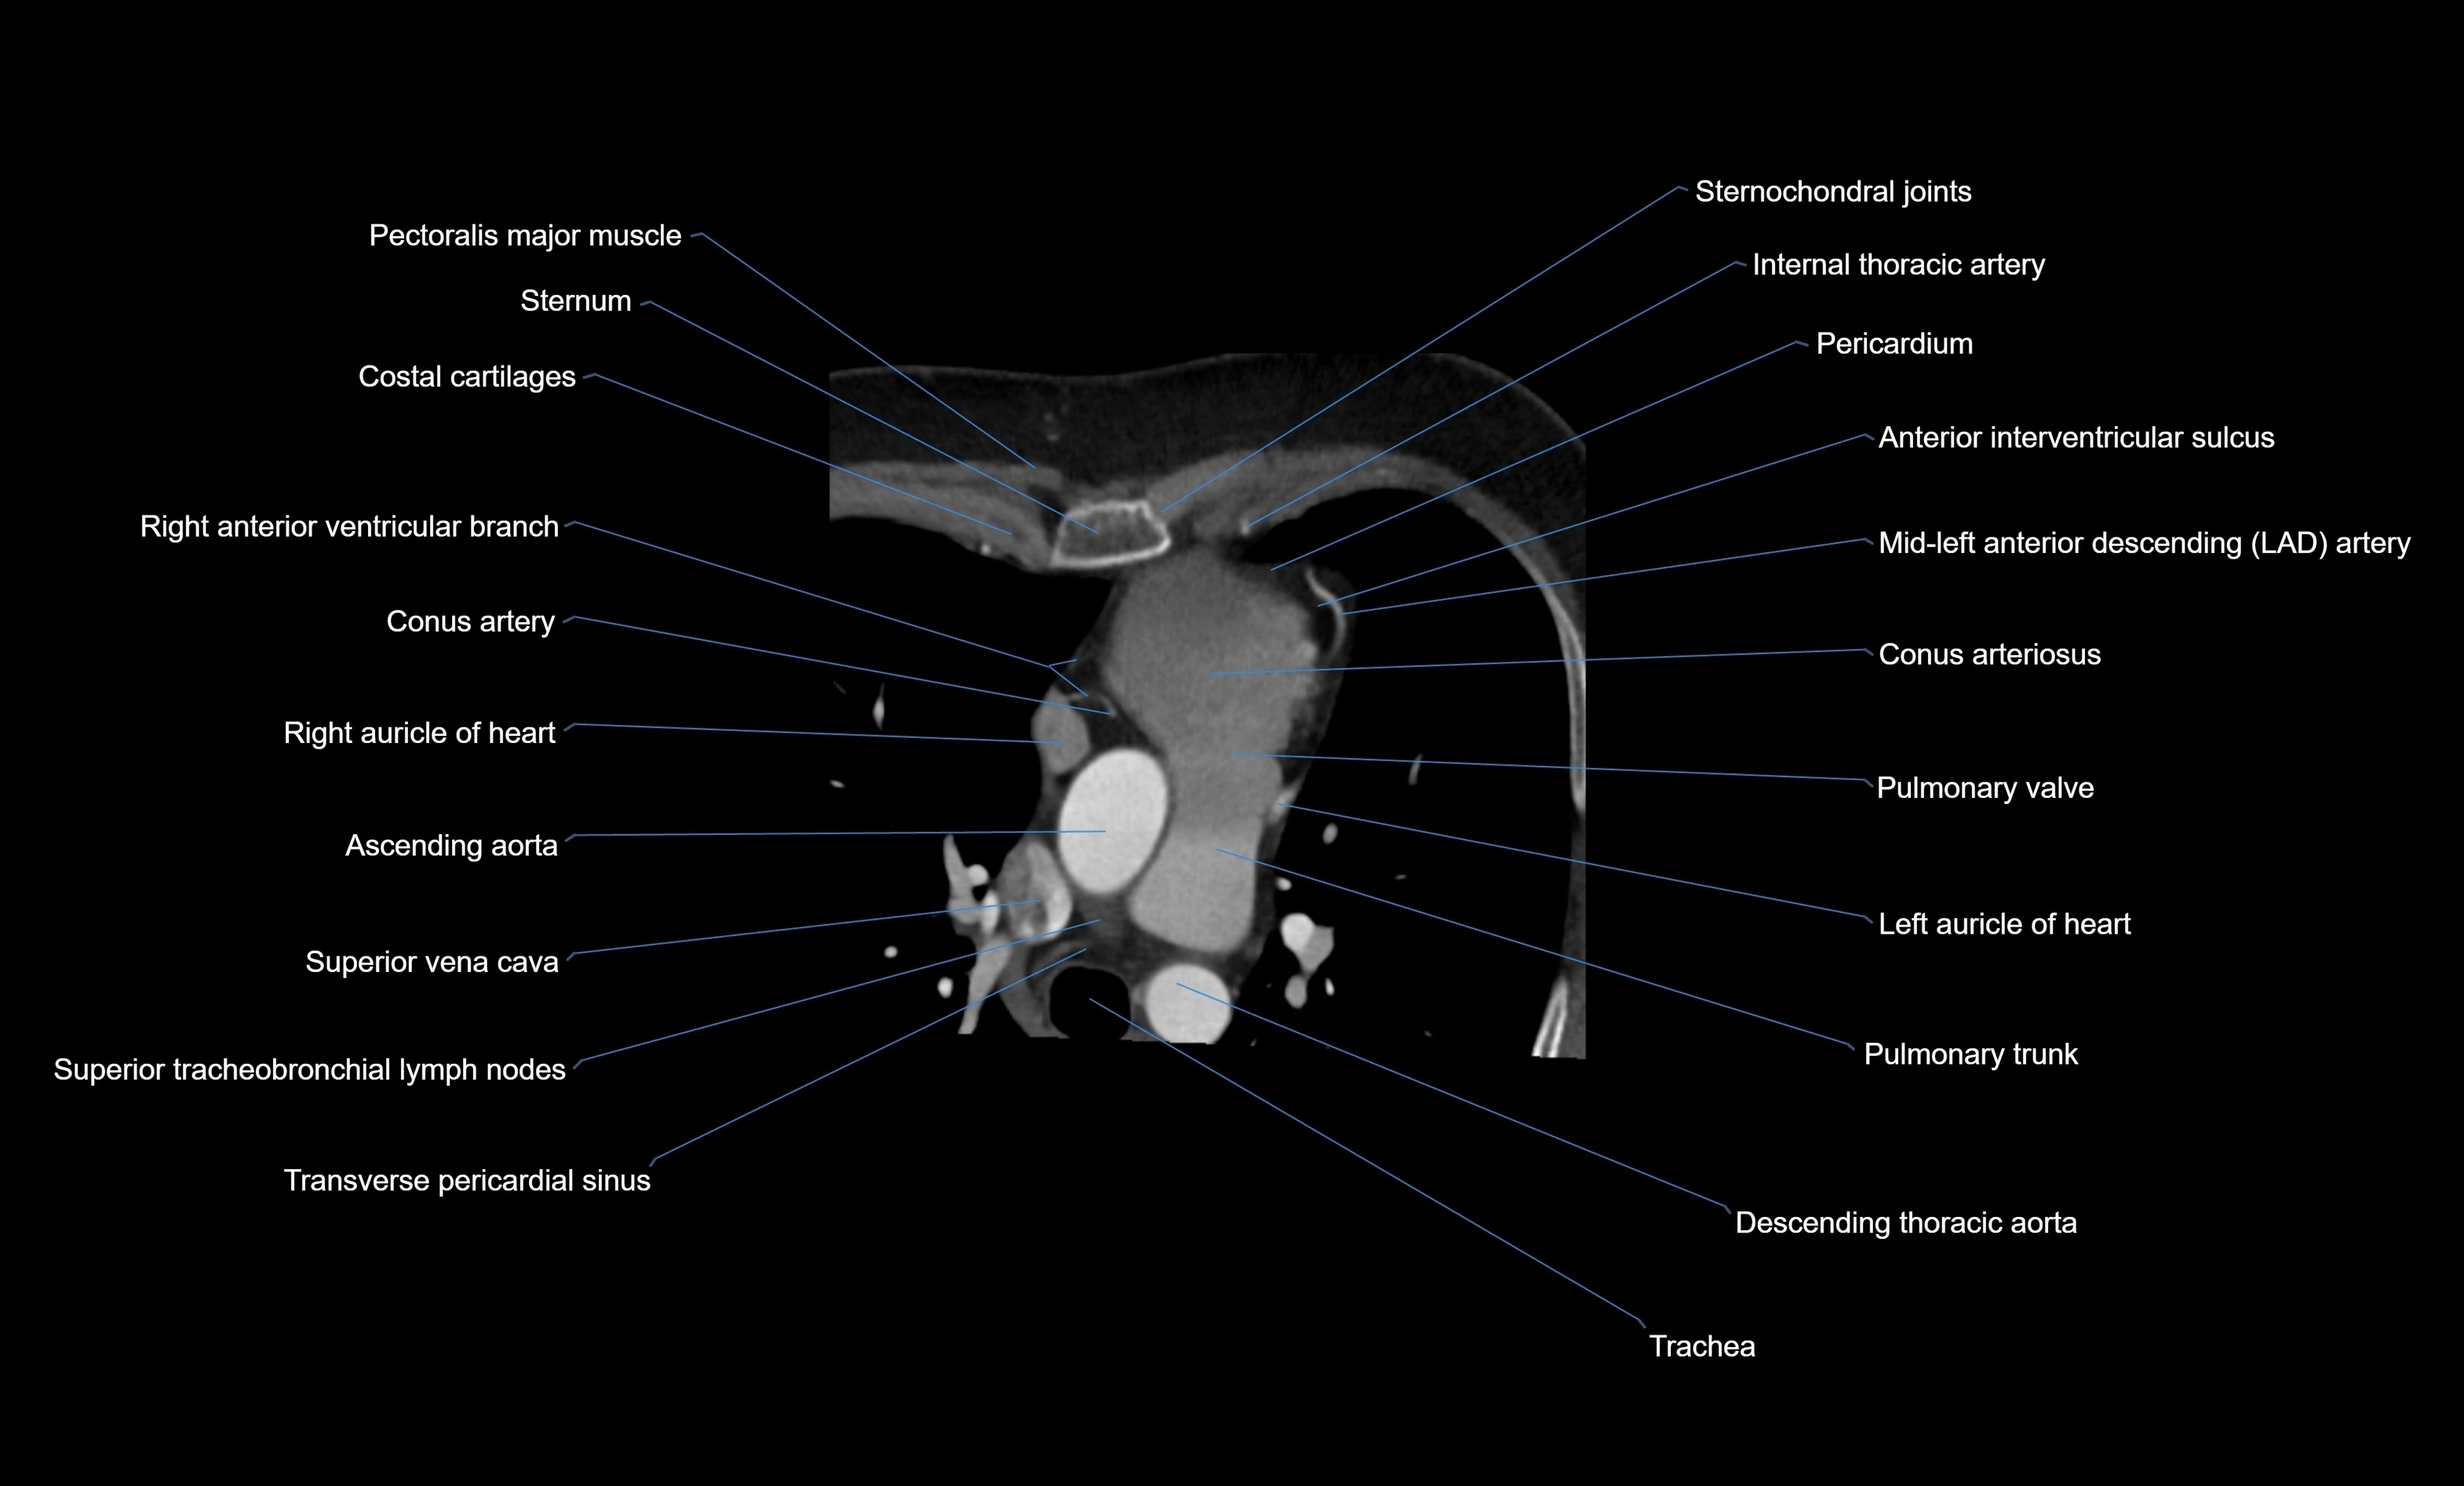

- Costal cartilages

- Sternum

- Conus arteriosus

- Conus artery

- Right auricle of heart

- Ascending aorta

- Superior vena cava

- Superior tracheobronchial lymph nodes

- Transverse pericardial sinus

- Pulmonary trunk

- Pulmonary valve

- Left atrium

- Left auricle

- Descending thoracic aorta